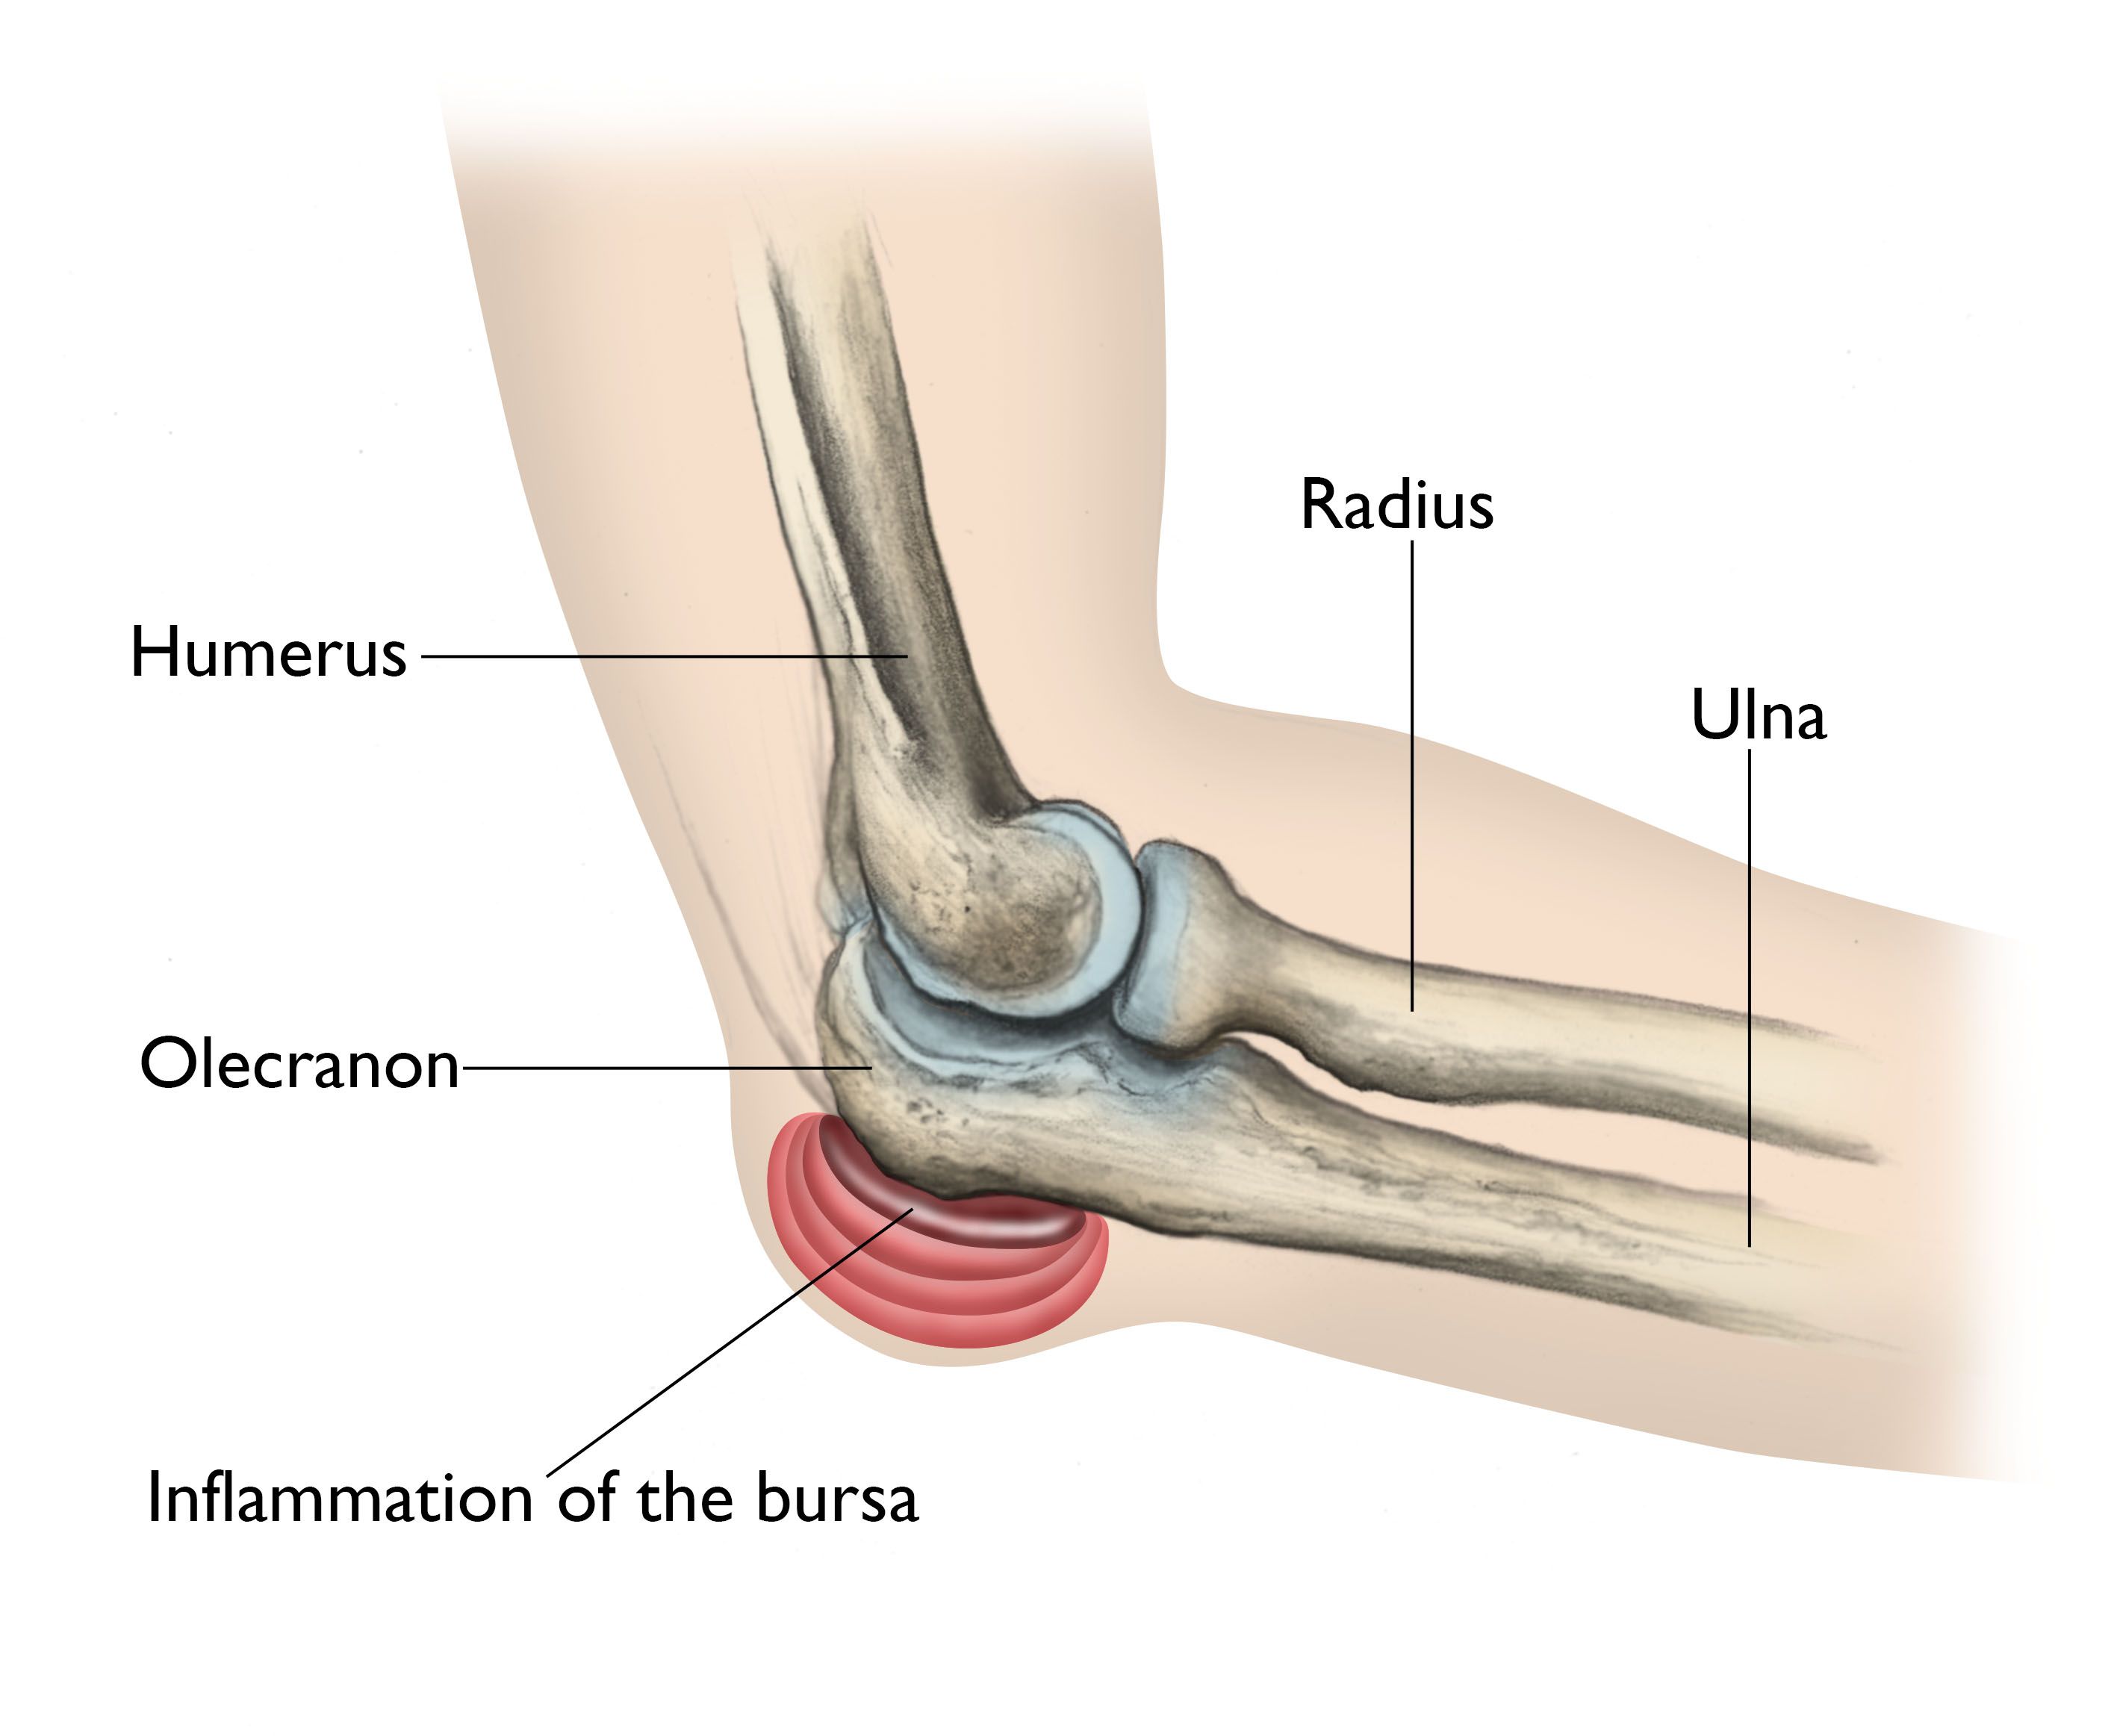

If you notice symptoms suggestive of a bone spur talk to your doctor about treatment. Tendinitis and bursitis of the elbow can cause swelling in these tissues.

Elbow Olecranon Bursitis Orthoinfo Aaos

Olecranon Bursitis Spur